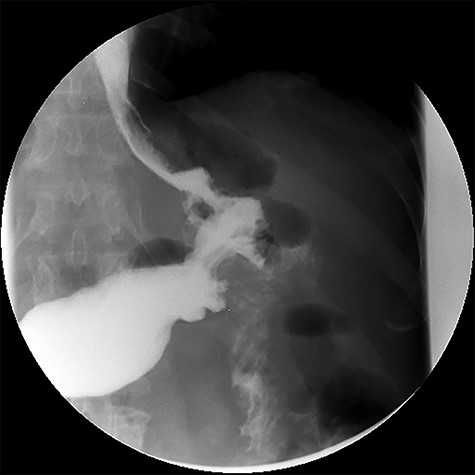

Three months after endoscopic treatment, the patient started complaining of epigastric pain again, without other gastrointestinal symptoms or weight regain. An upper gastrointestinal (GI) contrast swallow study showed recurrence of the GGF and GJA stenosis (see Fig. 4).

Upper gastrointestinal contrast swallow study image where it is possible to see a gastro-gastric fistula with opacification of the excluded stomach.

After treatment of the abdominal abscess with percutaneous drainage and antibiotics, an upper GI contrast swallow study confirmed persistency of the GGF without any spillage of contrast to the abdominal cavity (see Fig. 9). The patient was discharged, medicated with oral PPIs.

Upper gastrointestinal contrast swallow study image showing progression of contrast from the oesophagus to the gastric pouch and from the gastric pouch to the excluded stomach, confirming a gastro-gastric fistula.